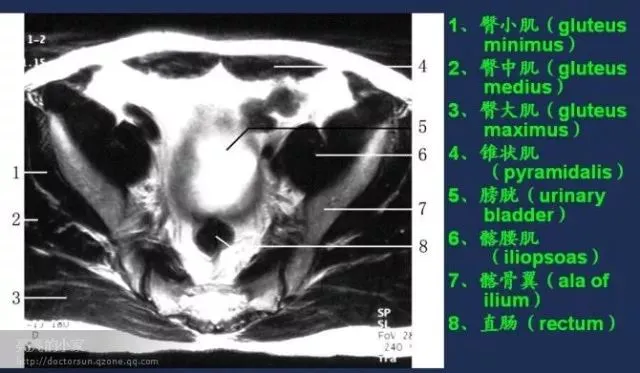

收藏!全身MRI解剖图谱,医生必备